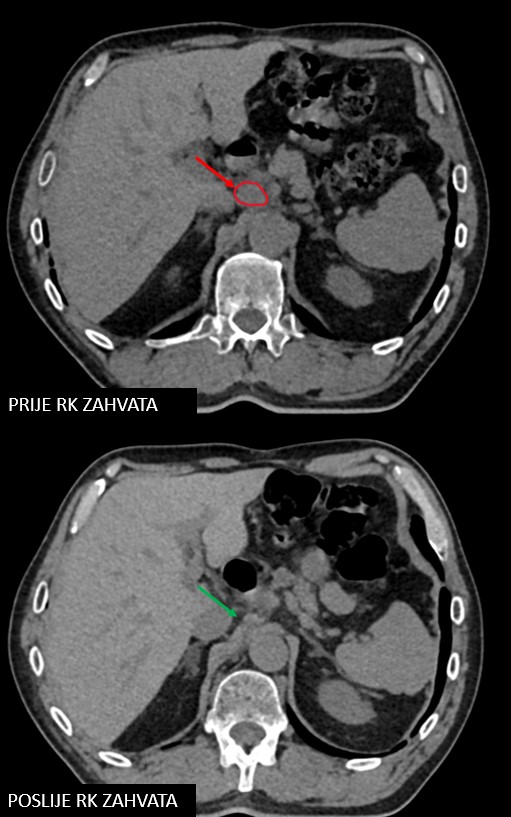

SBRT lymphonodi intraabdominalis (22.11. - 26.11.2021.)

Rezultat – 19 mjeseci nakon RK

Potpuni nestanak tretiranog limfnog čvora